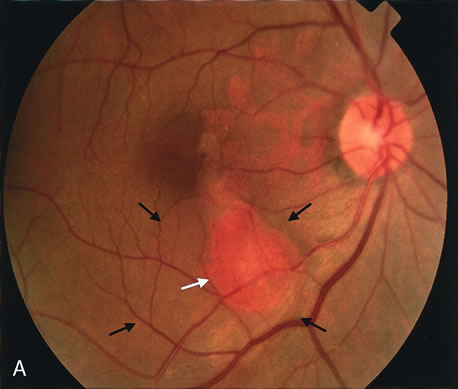

zone in senile macular degeneration. Am J Ophthalmol 93:157, 1982. 8. Yannuzzi LA, Negrão S, Iida T et al: Retinal angiomatous proliferation in age-related macular degeneration. Retina 21:416–434, 2001. 9. Fernandez LH, Freund KB, Yannuzzi LA et al: The nature of focal areas of hyperfluorescence or hot spots imaged with

indocyanine green angiography. Retina 22:557–568, 2002. 10. Ghazi NG. Retinal angiomatous proliferation in age-related macular degeneration. Retina 22:509–511, 2002. 11. Axer-Siegel R, Bourla D, Priel E et al: Angiographic and flow patterns of retinal choroidal anastomoses in age-related

macular degeneration with occult choroidal neovascularization. Ophthalmology 109:1726–1736, 2002. 12. Lafaut BA, Aisenbrey S, Vanden Broecke C et al: Clinicopathological correlation of deep retinal vascular anomalous complex

in age related macular degeneration. Br J Ophthalmol 84:1269–1274, 2000. 13. Slakter JS, Yannuzzi LA, Schneider U: Retinal choroidal anastomoses and occult choroidal neovascularization in

age-related macular degeneration. Ophthalmology 107:742–753, 2000. 14. Hartnett ME, Weiter JJ, Staurenghi G et al: Deep retinal vascular anomalous complexes in advanced age-related

macular degeneration. Ophthalmology. 103:2042–2053, 1996. 15. Kuhn D, Meunier I, Soubrane G et al: Imaging of chorioretinal anastomoses in vascularized retinal pigment epithelium